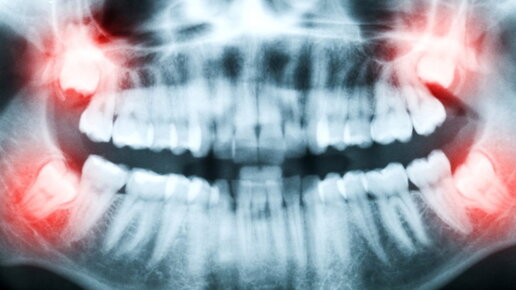

Зубы мудрости отличаются от других зубов как строением, так и особенностью прорезывания. Могут появляться в полной или частичной комплектации. У некоторых людей вовсе отсутствуют. Хорошо это или плохо — мнения ученых расходятся. Одни считают, что без восьмерок можно спокойно обойтись, другие отстаивают их важность в процессе формирования зубочелюстной системы. 🦕Стоматология в древности Необходимость лечения зубов имела место во все времена. Современная стоматология и ее подобие в древности — далеко не одно и то же...

До 16 лет у большинства людей челюстной ряд считается сформированным. Но есть еще зуб мудрости у человека, который начинает свой рост с этого времени, доставляя массу неприятных ощущений. С этого момента начинается завершающий этап. Разберем, сколько зубов мудрости у человека может вырасти и как долго это происходит. Не имеющие молочных предшественников последние жевательные элементы Начало прорезывания последних жевательных элементов происходит в 14-16 лет, у кого-то позже, в 20-28 лет. Все индивидуально...